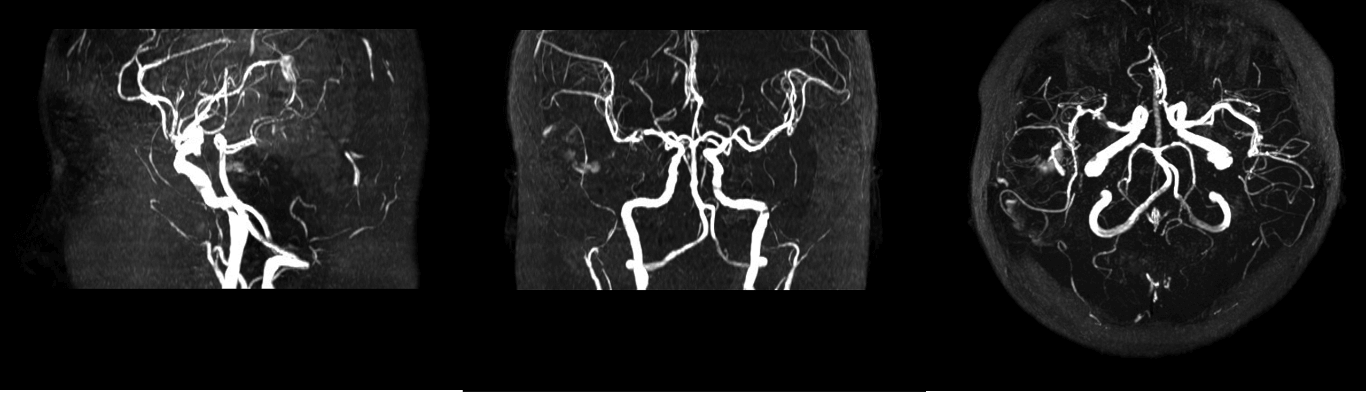

Angiography is an X-ray exam of the arteries and veins to diagnose blockages and other blood vessel problems. Combined with the use of some type of contrast medium injected via a catheter, the angiogram identifies areas of blockage or damaged vessels within the circulatory system. An angiogram could be used to discover aneurysms (an area of a blood vessel that bulges or balloons out), cerebral vascular disease (such as stroke or bleeding in the brain), or blood vessel malformations.

● Cerebral (brain) angiogram